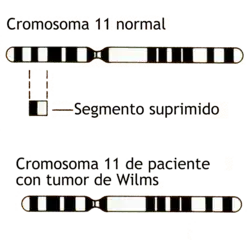

Se ha notado una asociación genética en muchos casos de nefroblastoma. A comienzos de los años 1970 se propuso un modelo genético como parte de la etiología de este tipo de cáncer, fundamentando en un gen de supresión tumoral alterado denominado WT1 localizado en el brazo corto del cromosoma 11p13.[4] Los cambios en este cromosoma predisponen al portador a un alto riesgo de trastornos congénitos, incluyendo el nefroblastoma.[5][6] Otros candidatos involucrados en la patogenia de esta enfermedad neoplásica renal incluyen las proteínas IGFII, H19 y p57kip2[7] y se han implicado otros cromosomas como el 16, 7 y 17.[1] Al menos la mitad de los pacientes con un tumor de Wilms y mutaciones en WT1 también cursan con mutaciones en el gen CTNNB1, que codifica el protooncogen β-catenina.[8]